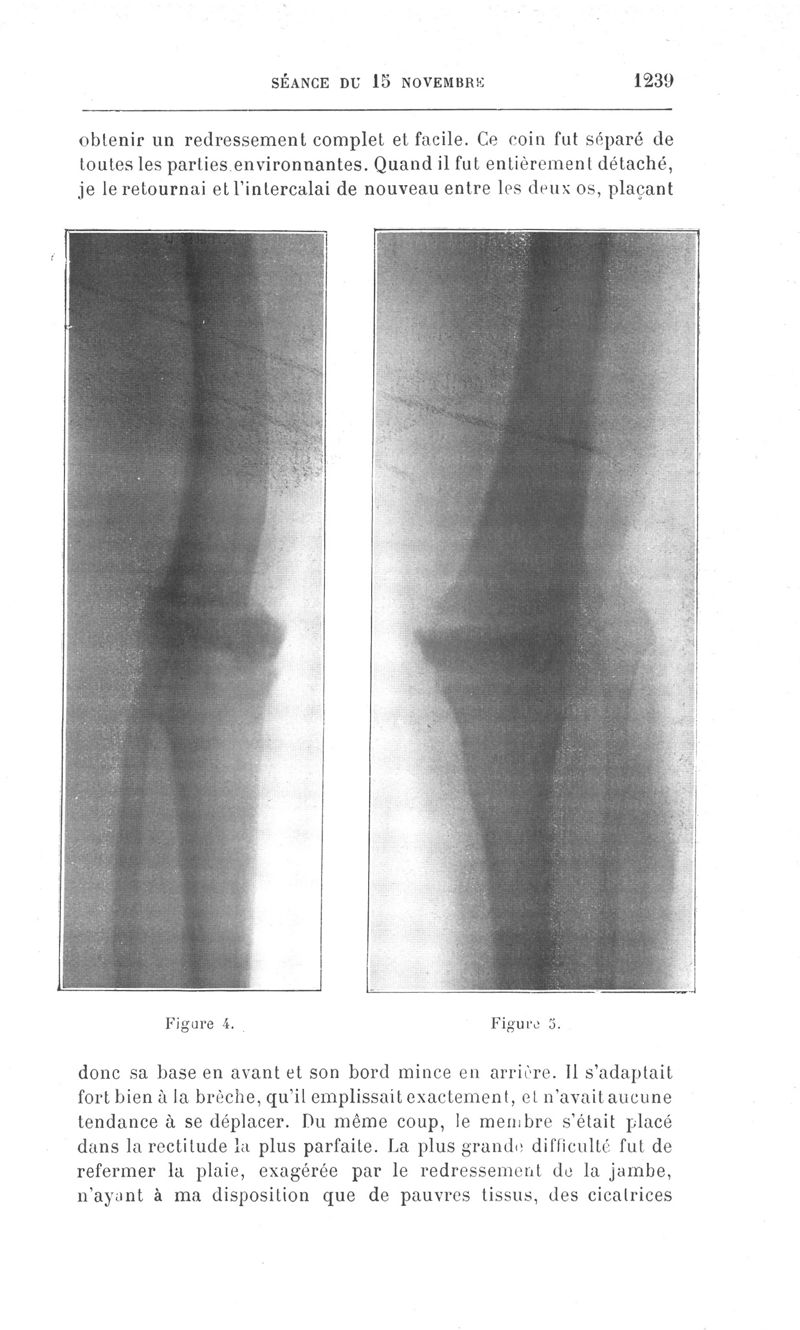

Bulletins et mémoires de la société de chirurgie de Paris

Tome XXXVII, 1911. - Paris : Masson, 1911.